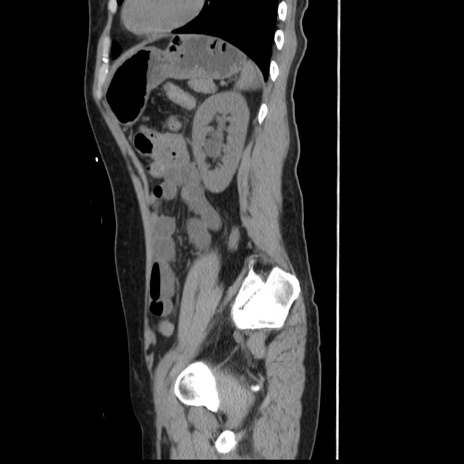

【症例】 50歳代女性

【主訴】 腹痛

【現病歴】前日生レバーを食べた。今朝に排便あり。 昼前に突然発症の腹痛を生じ、当院救急外来を受診した。

【既往歴】 子宮筋腫にてで子宮全摘後

【身体所見】 意識清明、腹部:平坦、軟、下腹部やや左を中心に圧痛・反跳痛あり、筋性防御あり

【データ】WBC 7800、CRP 0.07